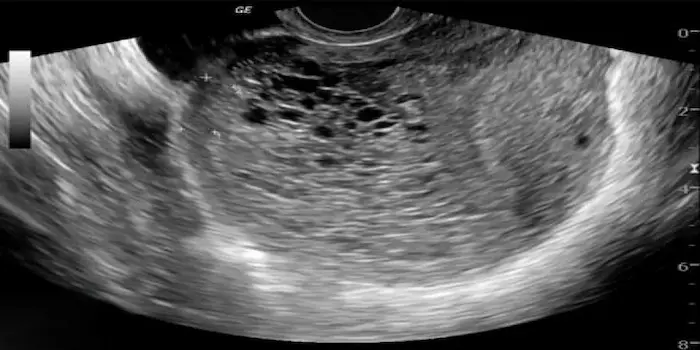

- الفحص بالموجات فوق الصوتية (السونار): يعتبر الطريقة الرئيسية لتشخيص الحمل العنقودي، حيث يظهر عبر الفحص عبر المهبل أو البطن مجموعة من الحويصلات داخل الرحم تشبه عناقيد العنب، وغالبًا لا يرى جنين أو كيس للسائل الأمنيوسي.